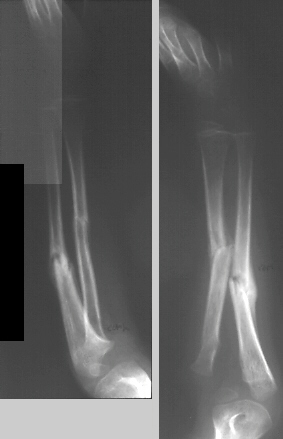

This is a 4 + 6mos old male who sustained a fall onto an outstretched left arm in December 1994 resulting in a Monteggia Type lV fracture. It was treated with closed reduction and casting. Subsequently, he went on to a malunion with a persistent dislocation of the radial head. He presented to A.I. duPont Institute10 months post injury for further evaluation and treatment.

On physical examination, he has a prominence over the left radial head. There is full flexion and extension. He has full pronation but lacks 30 degrees of full supination. He is neurovascularly intact.

XRAY FINDINGS:

The most important view is a true lateral of the elbow. The lesion may be missed on the AP view. In the lateral view, a line drawn through the center of the radial neck and head should extend through the capitelum. This is true whether the elbow is flexed or extended.